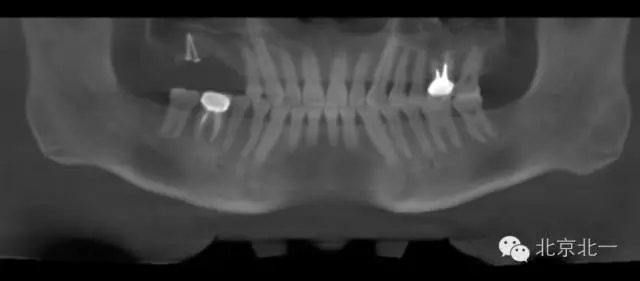

圖二:手術(shù)前全景片

CBCT顯示,骨寬度可,骨高度不足,月3mm。頜間距離增大。

檢查:15、16 缺失。17三度松動。

患者,男,30歲,右側(cè)上頜后牙區(qū)缺失,咨詢種植。